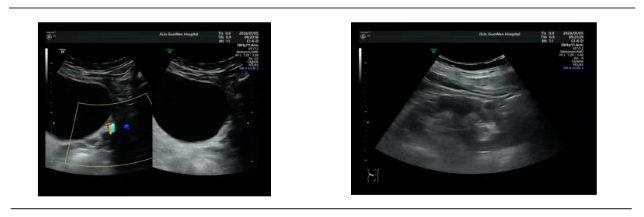

家住附近的李先生(化名),发病时正值午后,左侧腰腹突然传来剧烈绞痛,痛感一路蔓延到小腹,浑身冷汗直流,连路都走不了,甚至出现了尿频、排尿不适的症状。家人紧急送医后,泌尿系彩超明确病因:左侧输尿管下段结石,大小0.9cm,伴有轻微肾积水。

拿到结果的李先生(化名)十分发愁:身边有人结石开刀做手术,恢复期长又遭罪,自己工作繁忙,根本没时间休养;可放任不管,疼痛反复不说,医生告知积水加重会伤肾,进退两难。泌尿外科专家团队仔细评估后,给出了精准方案:患者结石位置、大小完全符合体外冲击波碎石指征,无需开刀手术,无创碎石就能解决问题。

不同于传统手术的创伤性,体外冲击波碎石打破了“结石必开刀”的固有认知。治疗时,李先生(化名)无需麻醉,全程躺卧即可,医生通过超声实时精准定位结石位置,体外冲击波穿透体表,精准作用于坚硬结石,利用物理效应将结石逐层击碎成泥沙状细小颗粒,全程仅30分钟,全程只有轻微酸胀感,完全没有想象中的剧痛。